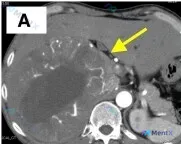

网上看到一份肾上腺和肝脏结节的影像资料,肝右叶有巨大分叶状占位,边界清、内部混杂密度,关键是周边和分隔处有典型的网格状/蜂窝状强化,大家先看看思路会不会被“巨大占位”带偏?